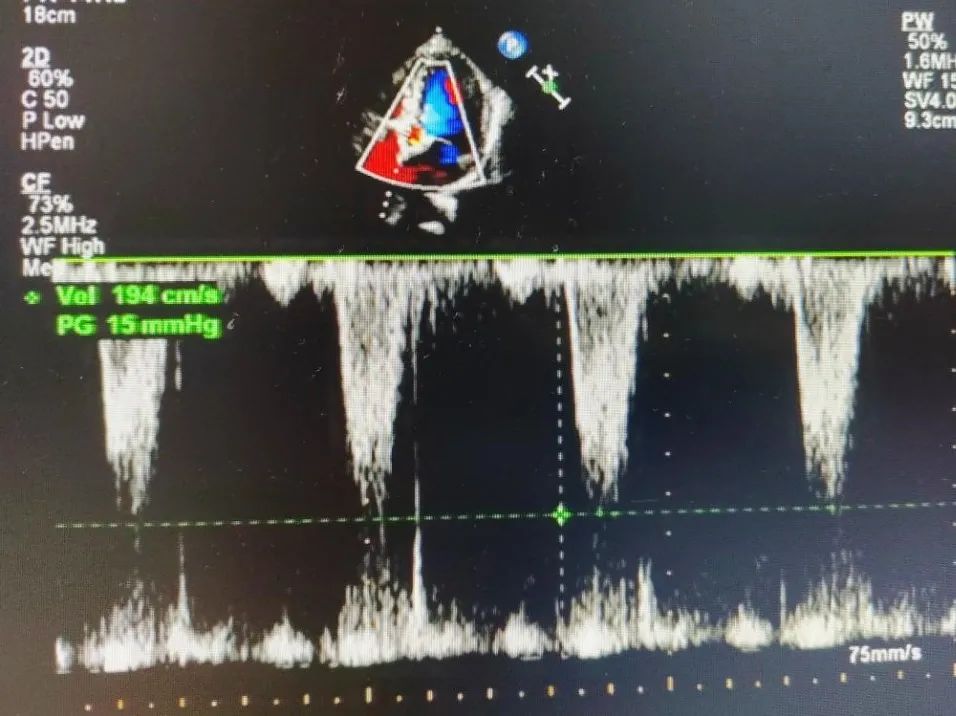

超声检查

• 左心房增大(左房径为40mm);

• 左室壁弥漫性增厚(14-16mm);

• 主动脉瓣退行性病变并重度狭窄;

• 主动脉瓣增厚;

• 二、三尖瓣及主动脉瓣少量反流;

• 左室舒张功能减低;

• 左室射血分数:59%;

• 主动脉瓣口前向血流速度:4.9m/s;

• 主动脉瓣跨瓣压差:96mmHg。

术中患者生命体征平稳,手术顺利完成。术后心超提示,释放后人工瓣膜正常工作,主动脉瓣跨瓣压差由术前的96mmHg改善至术后的0mmHg,主动脉瓣口前向血流速度由术前的4.9m/s改善至术后的1.9m/s,患者血流动力学得到明显改善。术前患者步行30米即感胸闷、呼吸困难,术后步行实验显示患者步行380米亦无任何不适,可见患者生存质量得到明显提高。